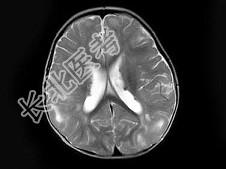

- 单项选择题男,1岁, 癫痫发作3次,智力反应低下, 头颅MRI扫描如图,最可能的诊断为 ( )

D、结节性硬化